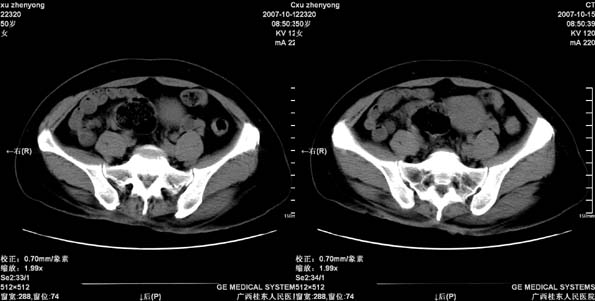

患者,女 50岁.会阴部坠胀感一月余,有痔疮病史,近期有便血;患者今年5月分结肠镜检查未见异常(由于患者不愿意ct增强扫描)没做增强,现准备手术,请各位老师会诊.

直肠壁明显增厚,呈块状表现,肠腔狭窄闭塞,考虑ca

直肠壁增厚明显,周围脂肪间隙模糊,见有小淋巴结显示,前方与阴道后壁分解不清。考虑直肠癌可能性大

不做强化,但平扫保留灌肠一定要做好。现在看直肠壁增厚明显,周围脂肪间隙模糊,前方与阴道后壁分界不清。考虑直肠癌可能性大